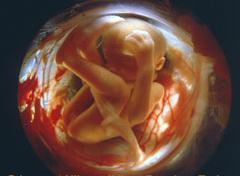

Третій триместр вагітності. 22-24 тижні вагітності.

У цей період відбувається розвиток слуху. костенеют слухові кісточки і починають проводити звуки. Чарівне диво цього періоду - це те, що крихта чує голос мами, биття її серця, її подих. На 24 тижні малюкові стають доступні і зовнішні звуки.

У період 22 тижні формуються жирові відкладення і дитина пристойно і активно набирає вагу. У дитини вже хороша координація. Також він / вона періодично засинає і прокидається.

У період 22-24 тижнів малюк вже здатний дихати самостійно, що підвищує його шанси при такому ранньому народженні на світло.

Щоб малюк зумів вижити в разі передчасних пологів, його поміщають в палату інтенсивної терапії. Якщо крихта народиться на 22 Нелі, то є серйозний ризик виникнення захворювань функціональних органів. При народженні на 24 Нелі 8 з 10 малюків виживають і мають багато шансів на здорове життя.

Третій триместр вагітності. 26-28 тижні вагітності.

Малюк активно реагує на зовнішні звуки і світло. вже відкриваються очі. Кроха смокче пальчик і навіть плаче.

На даному етапі центральна нервова система досить розвинена, щоб мозок контролював процес дихання, температуру тіла і інші рефлекторні функції.

Показники плода на 26-28 тижні вагітності вже прідліжени до рівня доношених дітей.

Майже всі діти, народжені в цей період можуть, в принципі, вижити, але з допомогу медиків.

Третій триместр вагітності. 30-32 тижні вагітності.

Плід стає зовсім схожий на крихітного чоловічка: шкіра ущільнюється, вушка набувають все більш звичну форму, очі під час бодорствованія знаходяться відкритими, а під час сну - закритими.

Тельці малюка дуже швидко зростає. Нервова система завершує своє формування, у крихти з'являються все нові рефлекторні реакції.

Багато діток, народжені в цей період виживають і виростав здоровими. Відразу після дострокового народження потрібна допомога медиків.